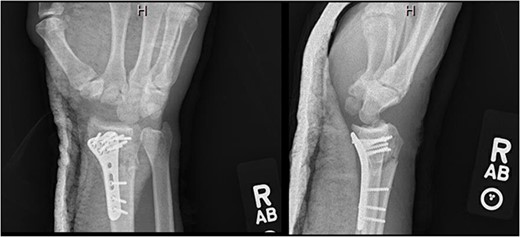

After medical optimization, the patient underwent PRC, open reduction internal fixation (ORIF) of the right distal radius fracture, and carpal tunnel release. A dorsal approach was used, with the third and fourth extensor compartments being released. At this point, extensive disruption of the dorsal wrist capsule and proximal carpal row was observed. The lunate was identified, noted to be devoid of soft tissue attachments, and was able to be excised. Completion of the PRC was achieved by excising the scaphoid and triquetrum from their minimal remaining soft tissue attachments entirely through the dorsal approach (Fig. 3). The lunate fossa of the radius, proximal capitate, and radioscaphocapitate ligament (prerequisite for successful acute PRC) was noted to be intact [2].

AP and lateral views immediately postop demonstrating right distal radius fixation and PRC.

At 3-month postoperative follow-up, grip strength was 18 lbs on the right and 25 lbs on the left. Pinch strength was 9 lbs on the left and 7 lbs on the right. At 5-month follow-up, the patient was transporting himself using a wheelchair, and his wrist pain was well controlled. At 7-month follow-up, grip strength was improved to 30 lbs on the right and 45 lbs on the left; pinch strength was 3 lbs on the right and 8 lbs on the left. Right wrist motion demonstrated 40° of flexion, 20° of extension, and full unlimited pronosupination. Radiographs demonstrated a healed distal radius fracture with no signs of arthrosis at the new radiocarpal joint (Fig. 4). At 1-year follow-up, the patient continued to progress functionally with no new complaints of pain. At 2-year follow up, the patient’s Disabilities of the Arm, Shoulder, and Hand score was 35.83.

AP and lateral views at 7-month follow-up demonstrating a healed right distal radius fracture without arthrosis at the new radiocarpal joint.